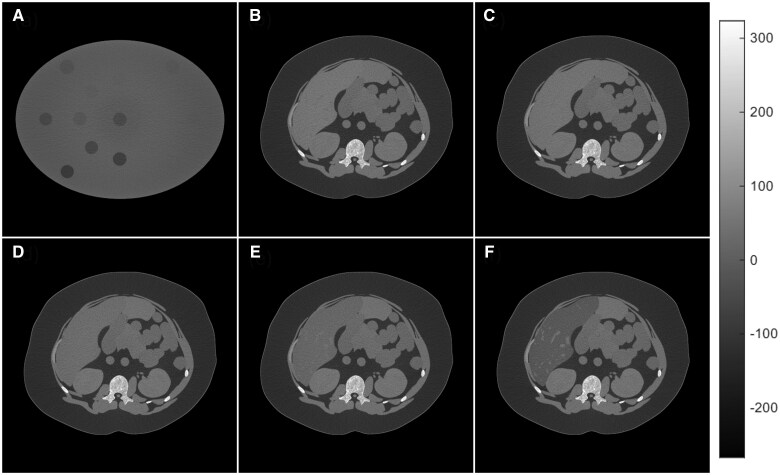

Materials and methods: dSi-PCCT is a cutting-edge photon-counting CT (GE HealthCare), with several investigational systems installed globally, used under IRB approval for imaging animals and human volunteers to support FDA clearance. We developed a dSi-PCCT simulator and benchmarked its imaging performance with respect to a prototype. We imaged a computational Gammex phantom with fat fractions (FF) ranging from 0% to 100%, along with five XCAT human models with liver FF ranging from 1% to 50%, using an abdominal CT protocol. The resulting spectral sinograms were processed using a material decomposition (MD) technique. We calculated HU-based Proton Density Fat Fraction (PDFF) from single-energy images in XCAT models and compared it against the MD-derived FF. The MD-derived FF of both datasets was assessed against the digitally defined ground truth values.

Results: We observed a strong correlation (R 2 = 0.98) between MD-derived, HU-based PDFF, and ground-truth FF in a Gammex and XCAT models. There was no statistically significant difference (P = .52) in FF quantification accuracy between Gammex and the XCAT human models. The root mean square errors were 4.7% for Gammex and 2.7% for XCAT. Bland-Altman analysis further confirmed good agreement between the ground truth and MD-derived FF, with differences in FF ranging from -6.9% to 7% for Gammex and -3.0% to 37.6% for XCAT.

Conclusion: The results indicate that dSi-PCCT could enable accurate liver fat quantification across a wide range of FFs in multiple objects. These findings suggest that the potential utility of dSi-PCCT for accurate liver fat assessment should be explored in vivo.